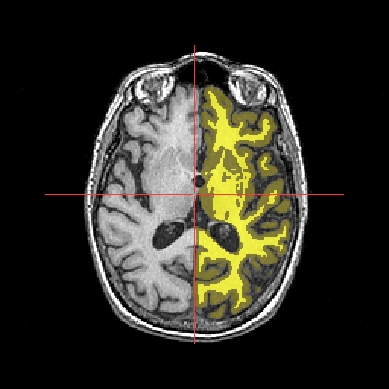

Application: Superimposing an anatomy and regions of interest (grey central nuclei)¶

In the following example, 3 objects are loaded in Anatomist:

Object1 (O1): anatomy

Object2 (O2): regions of interest graph drawn from the anatomy. So these 2 objects are in the same referential.

Object3 (O3): nomenclature to associate colors to regions of interest according to their name. This object does not have to be put in a window. Link between names in the nomenclature and in regions of interest is done automatically by Anatomist.

These 2 objects are in the same coordinates system, so they will be placed in the same referential, that is to say they will have the same color circle (red by default).